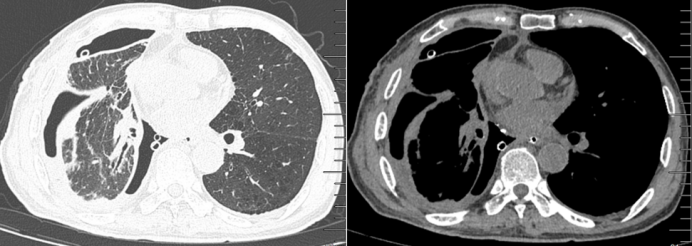

2024年8月29日,患者呼吸困难再次加重。胸部CT示:食管和右侧胸腔连通(图5)。急诊胃镜示:距门齿31 cm可见一食管瘘口(0.7 cm),窦腔,可见较多脓性分泌物及胸腔引流管,于瘘口处置入引流管(图6)

图片

5  胸部CT(2024-08-29)

2025年1月2日复查胸部CT:肺部炎症有所吸收(图7)停用抗生素。

7  胸部CT(2025-01-02)